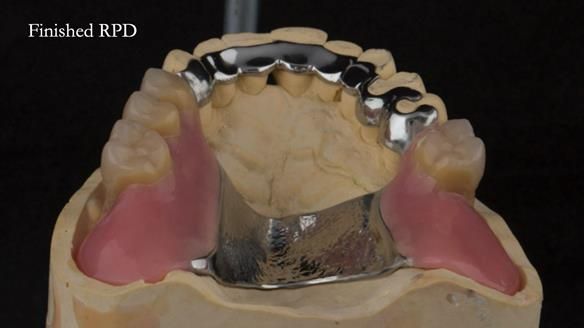

A metal-based upper RPD was made,

with metal backings incorporated to future-proof the design

should further teeth fail.

The way Rowan lengthened the teeth — particularly in the upper RPD — to match the existing gingival recession on the remaining teeth was superb. The dentures sit naturally within the context of the rest of the mouth.